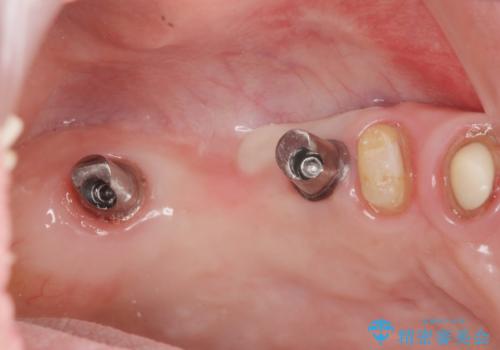

セラミック・インプラント治療を含む包括歯周病治療

残すことのできる歯できない歯を選別し、欠損部にはインプラントによる咬合機能の回復、保存できる歯には歯周病治療・根管治療を行う治療計画としました。

インプラント治療の注意事項(リスク・副作用など)

- 外科手術のため、術後に痛みや腫れ、違和感を伴います

- メンテナンスを怠ったり喫煙により、お口の中に大きな悪影響を及ぼすインプラント周囲炎等にかかる可能性があります